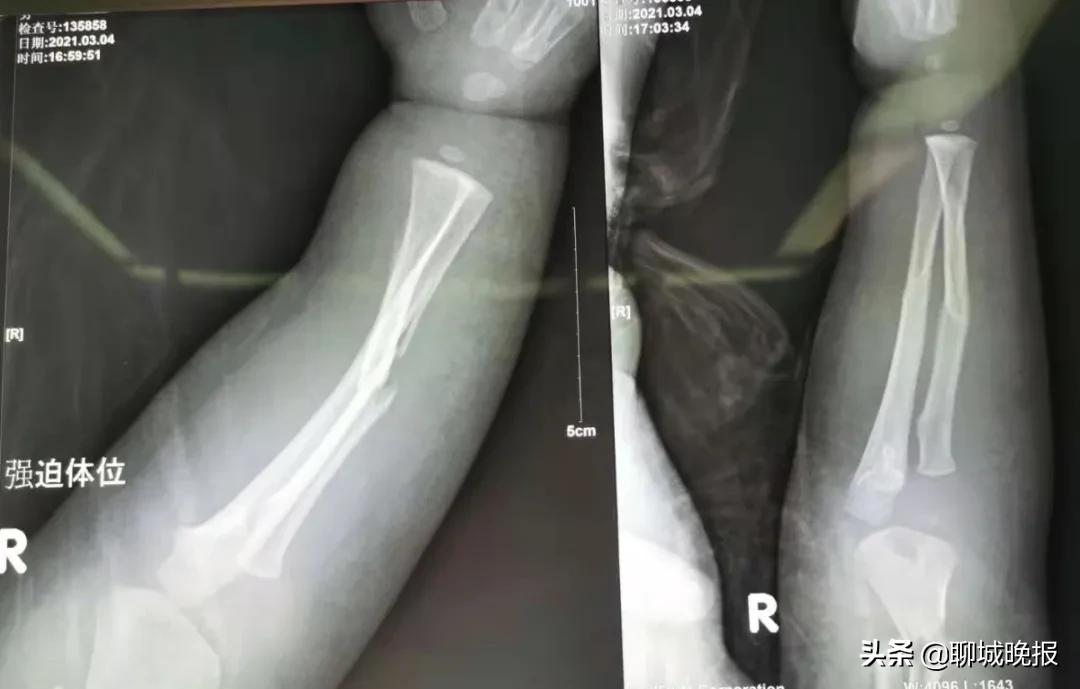

原来,3月4日下午,患儿在玩耍时看到转动的机器,非常好奇,趁大人一个不留意便伸手摸了上去,结果被绞伤导致右臂粉碎性骨折,遂来我院就医,诊断为右肱骨干粉碎性骨折,右尺桡骨骨折,右第2、3、5掌骨骨折。

术前 ↑ 术后 ↓ 对比